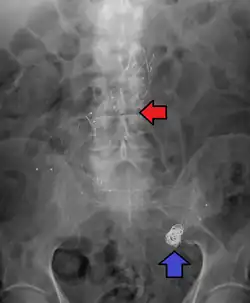

Abdominal aortic aneurysm involves a regional dilation of the aorta and is diagnosed using ultrasonography, computed tomography, or magnetic resonance imaging. A segment of the aorta that is found to be greater than 50% larger than that of a healthy individual of the same sex and age is considered aneurysmal.[9] Abdominal aneurysms are usually asymptomatic but in rare cases can cause lower back pain or lower limb ischemia.